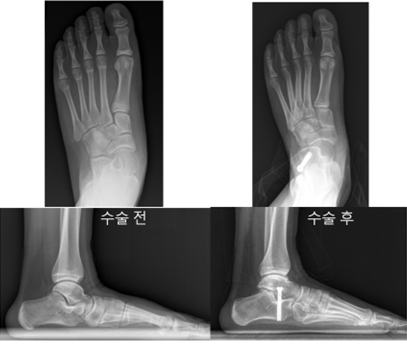

이에, 연구팀은 두 수술법의 치료 결과를 비교하기 위해 2003년부터 2022년까지 평발 교정 수술을 받은 10~14세 소아 환자 127명(총 223족)을 대상으로 연구를 진행했다. 수술 전후의 발 모양과 기능 변화를 확인하고자 방사선 사진과 삶의 질 평가 설문(OAFQ)을 통해 분석하고, 회복 기간과 합병증 발생 여부를 함께 비교했다.

연구 결과, 두 수술법 모두 평발을 교정하는 데 효과적인 것으로 나타났다. 두 환자군 모두에서 발 아치와 정렬을 나타내는 방사선 사진 수치들이 수술 후 크게 개선됐으며, 삶의 질 평가에서도 신체 기능, 학교생활 및 놀이, 정서적 측면, 신발 착용 등 모든 영역에서 점수가 향상된 것을 확인할 수 있었다.

하지만 회복 속도에서는 두 수술법 간 차이가 있었다. 종골 정지술을 받은 환자군은 체중 부하가 가능해 정상적으로 보행하기까지 평균 17.6일이 걸렸고, 종골 연장술을 받은 환자군은 평균 42.9일로 회복 속도에 유의미한 차이를 보였다. 또한, 종골 정지술을 받은 환자군에서 절골부의 불유합(뼈가 붙지 않는 상태) 등 주요 합병증의 발생 비율이 더 낮은 것으로 나타났다.

다만, 연구팀은 종골 정지술의 경우 수술 후 약 3년이 지나 발 성장이 마무리되는 시점에, 삽입한 나사를 제거하는 추가 수술이 필요하다는 점도 함께 고려해야 한다고 설명했다. 그럼에도 불구하고, 종골 정지술은 절개 범위가 크지 않아 회복이 빠르고, 주요 합병증 위험이 비교적 낮다. 교정 효과 또한 안정적으로 유지돼 소아 평발 환자에게 우선적으로 고려해볼 수 있는 것을 확인할 수 있었다.